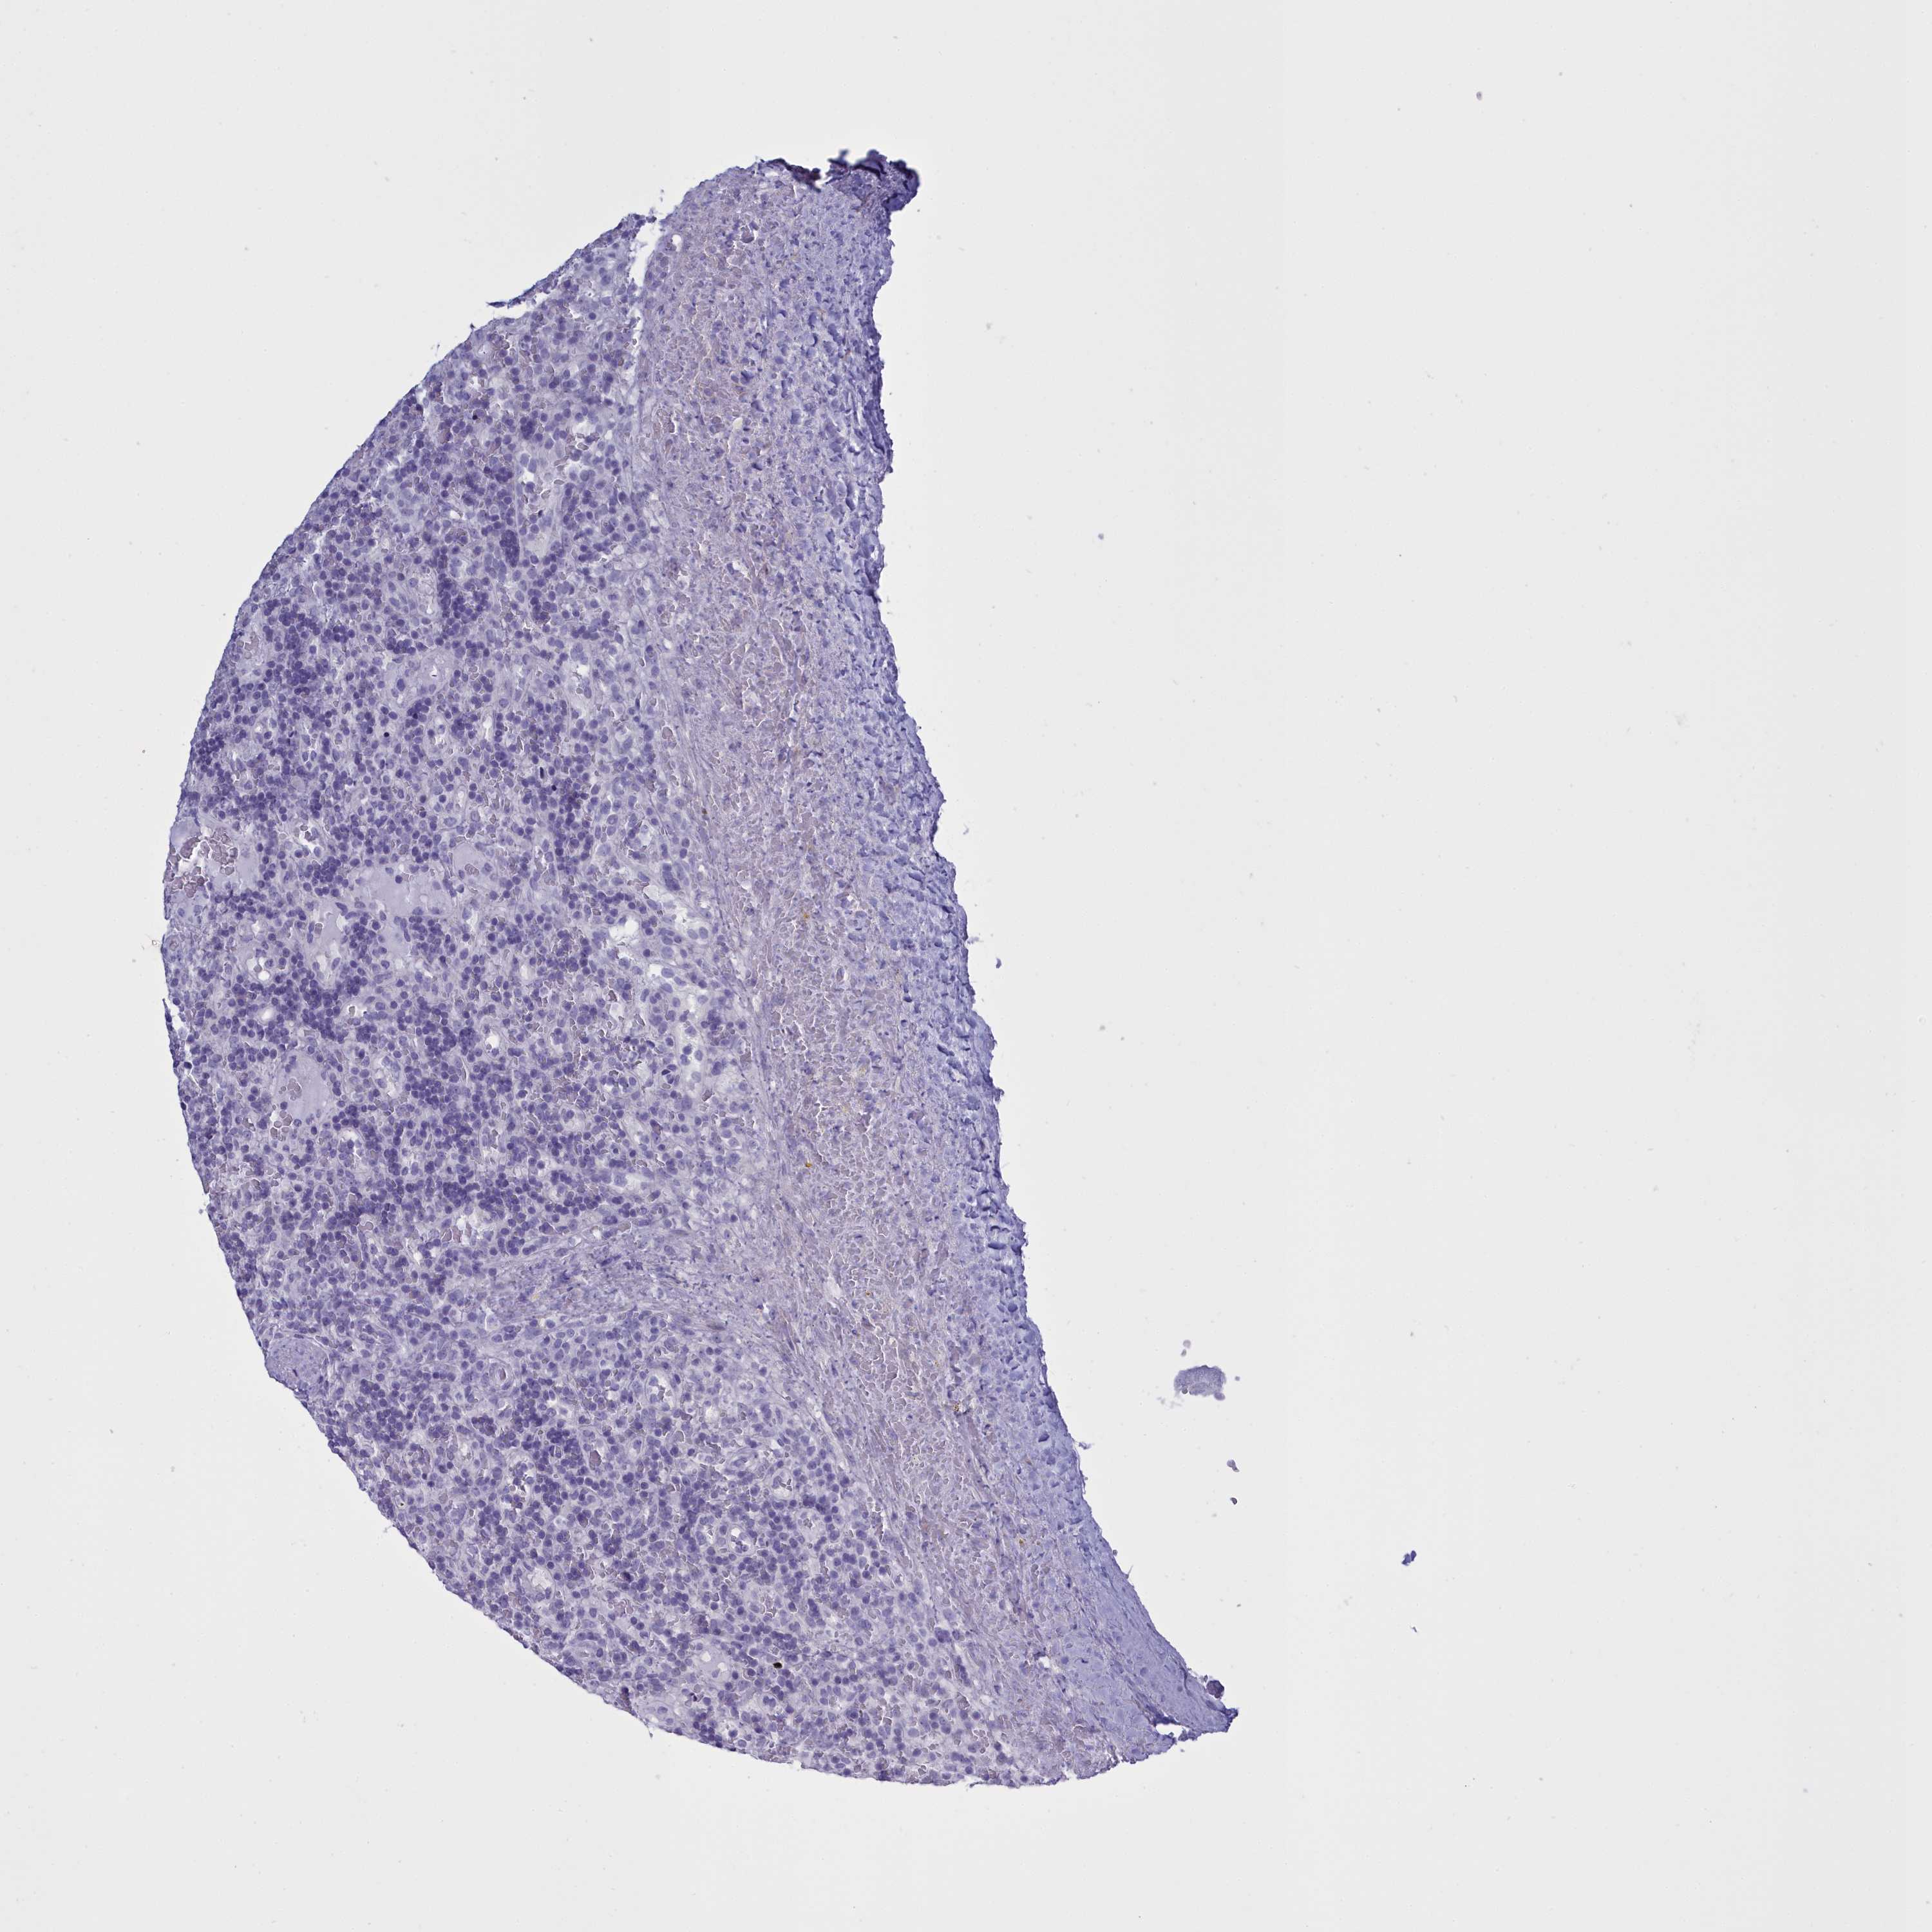

CANCER LYMPHOMA Show tissue menu

LYMPHOMA - Protein expressioni

A mouse-over function shows sample information and annotation data. Click on an image to view it in a full screen mode. Samples can be filtered based on level of antibody staining by selecting one or several of the following categories: high, medium, low and not detected. The assay and annotation is described here.

Antibody stainingi

Antibody staining in the annotated cell types in the current human tissue is reported as not detected, low, medium, or high, based on conventional immunohistochemistry profiling in selected tissues. This score is based on the combination of the staining intensity and fraction of stained cells.

Each image is clickable and will lead to virtual microscopy that enables deeper exploration of all samples and also displays staining intensity scores, fraction scores and subcellular localization as well as patient and tissue information for each sample.